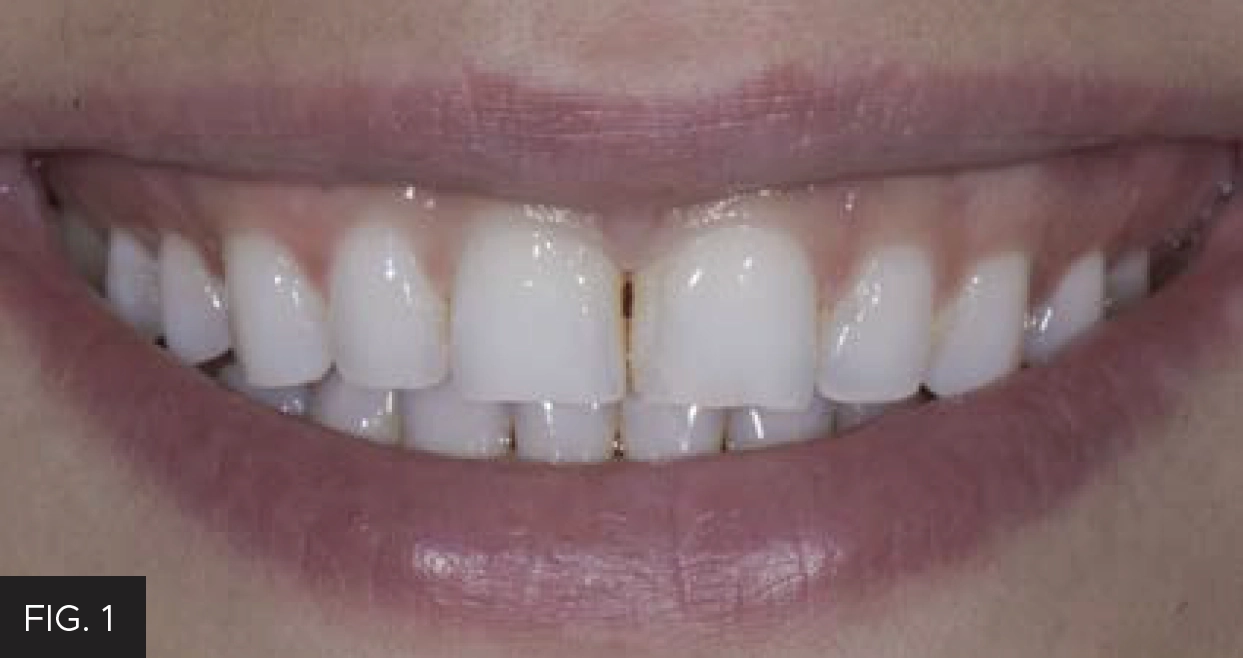

Such was the case when a young woman presented as a new patient seeking options to improve the appearance of her “flat front teeth”. (FIG. 1)

A young woman presented for treatment options to “fix her flat front teeth”. The accepted treatment plan involved short-term aligner therapy followed by a midline diastema closure and lengthening of the maxillary central incisors.